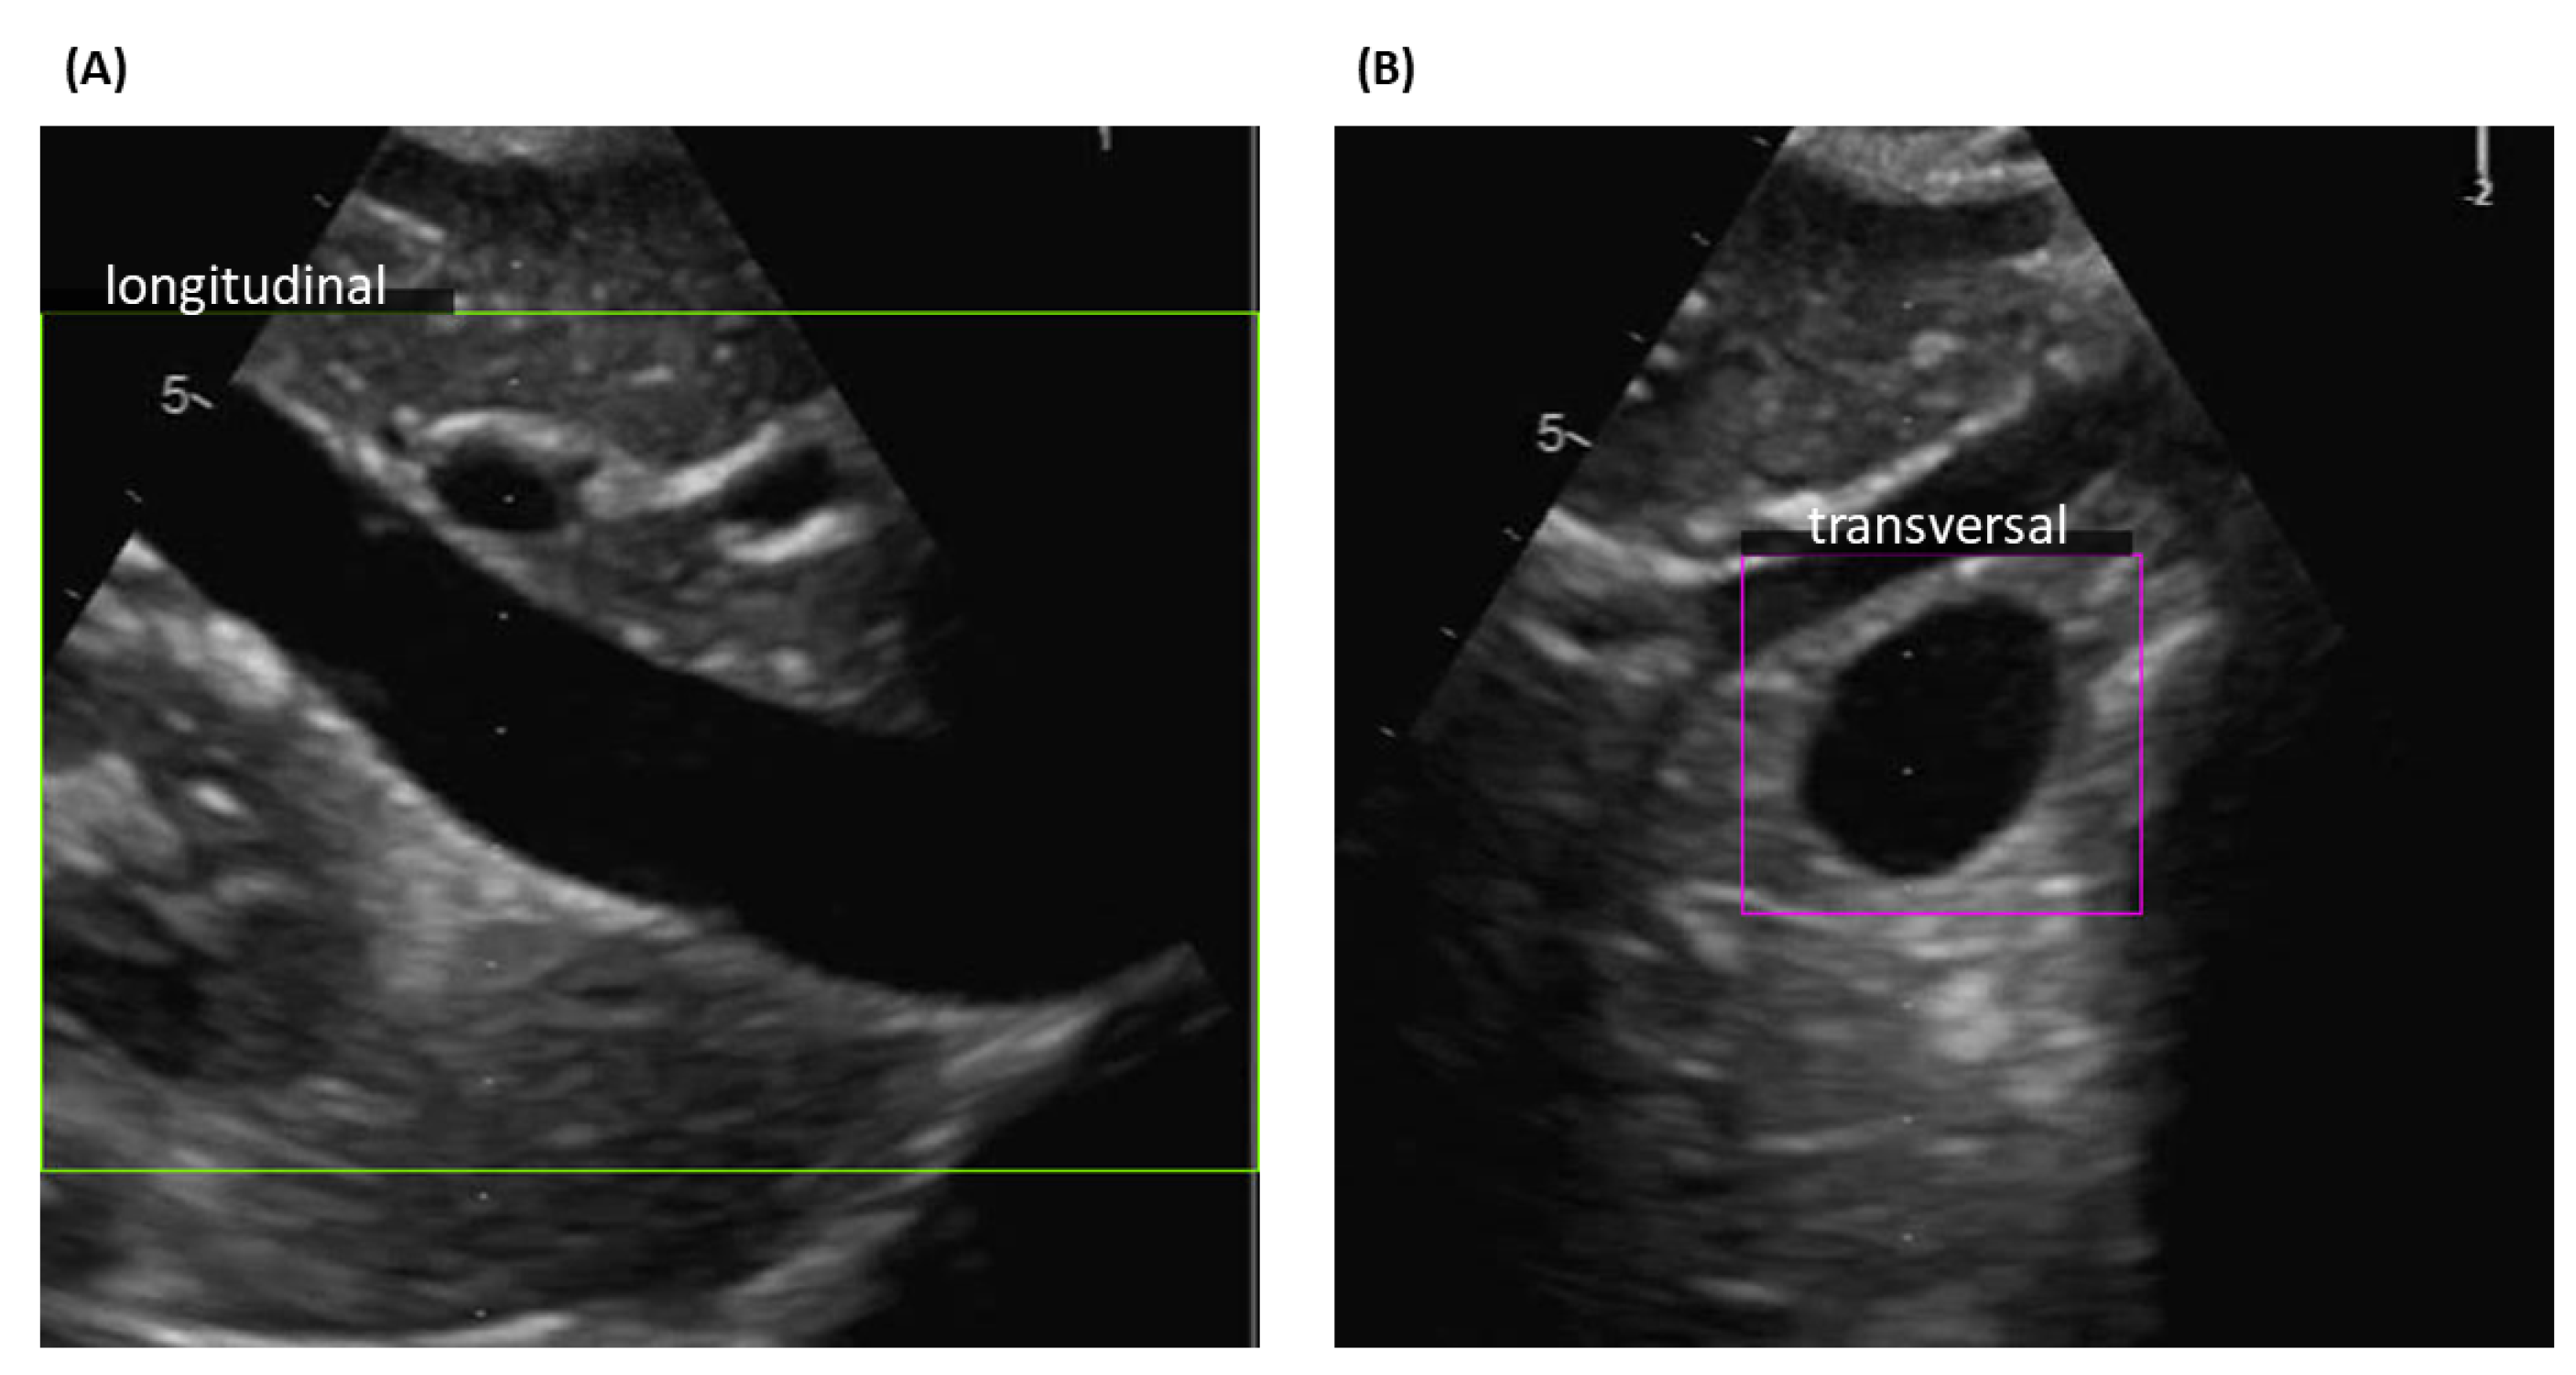

The YOLO networks trained on each of our three datasets were applied to classify the images into two categories, longitudinal or transverse view, and to detect the location of the IVC. An example of IVC detection is shown in Figure 2. The boundaries, green for the longitudinal view and violet for the transversal view, demarcate the regions where the vein is identified. Usually, the position of the vein is around the centre of the frame, but this is not always the case, as shown in the examples reported in Figure 3. YOLO networks examine each box in which the frame is split without having information on its location: thus, there is no bias in detecting the IVC in a specific location.

Figure 2.

Examples of YOLO detection outputs. (A) Longitudinal and (B) Transversal view of IVC and their respective detected areas.